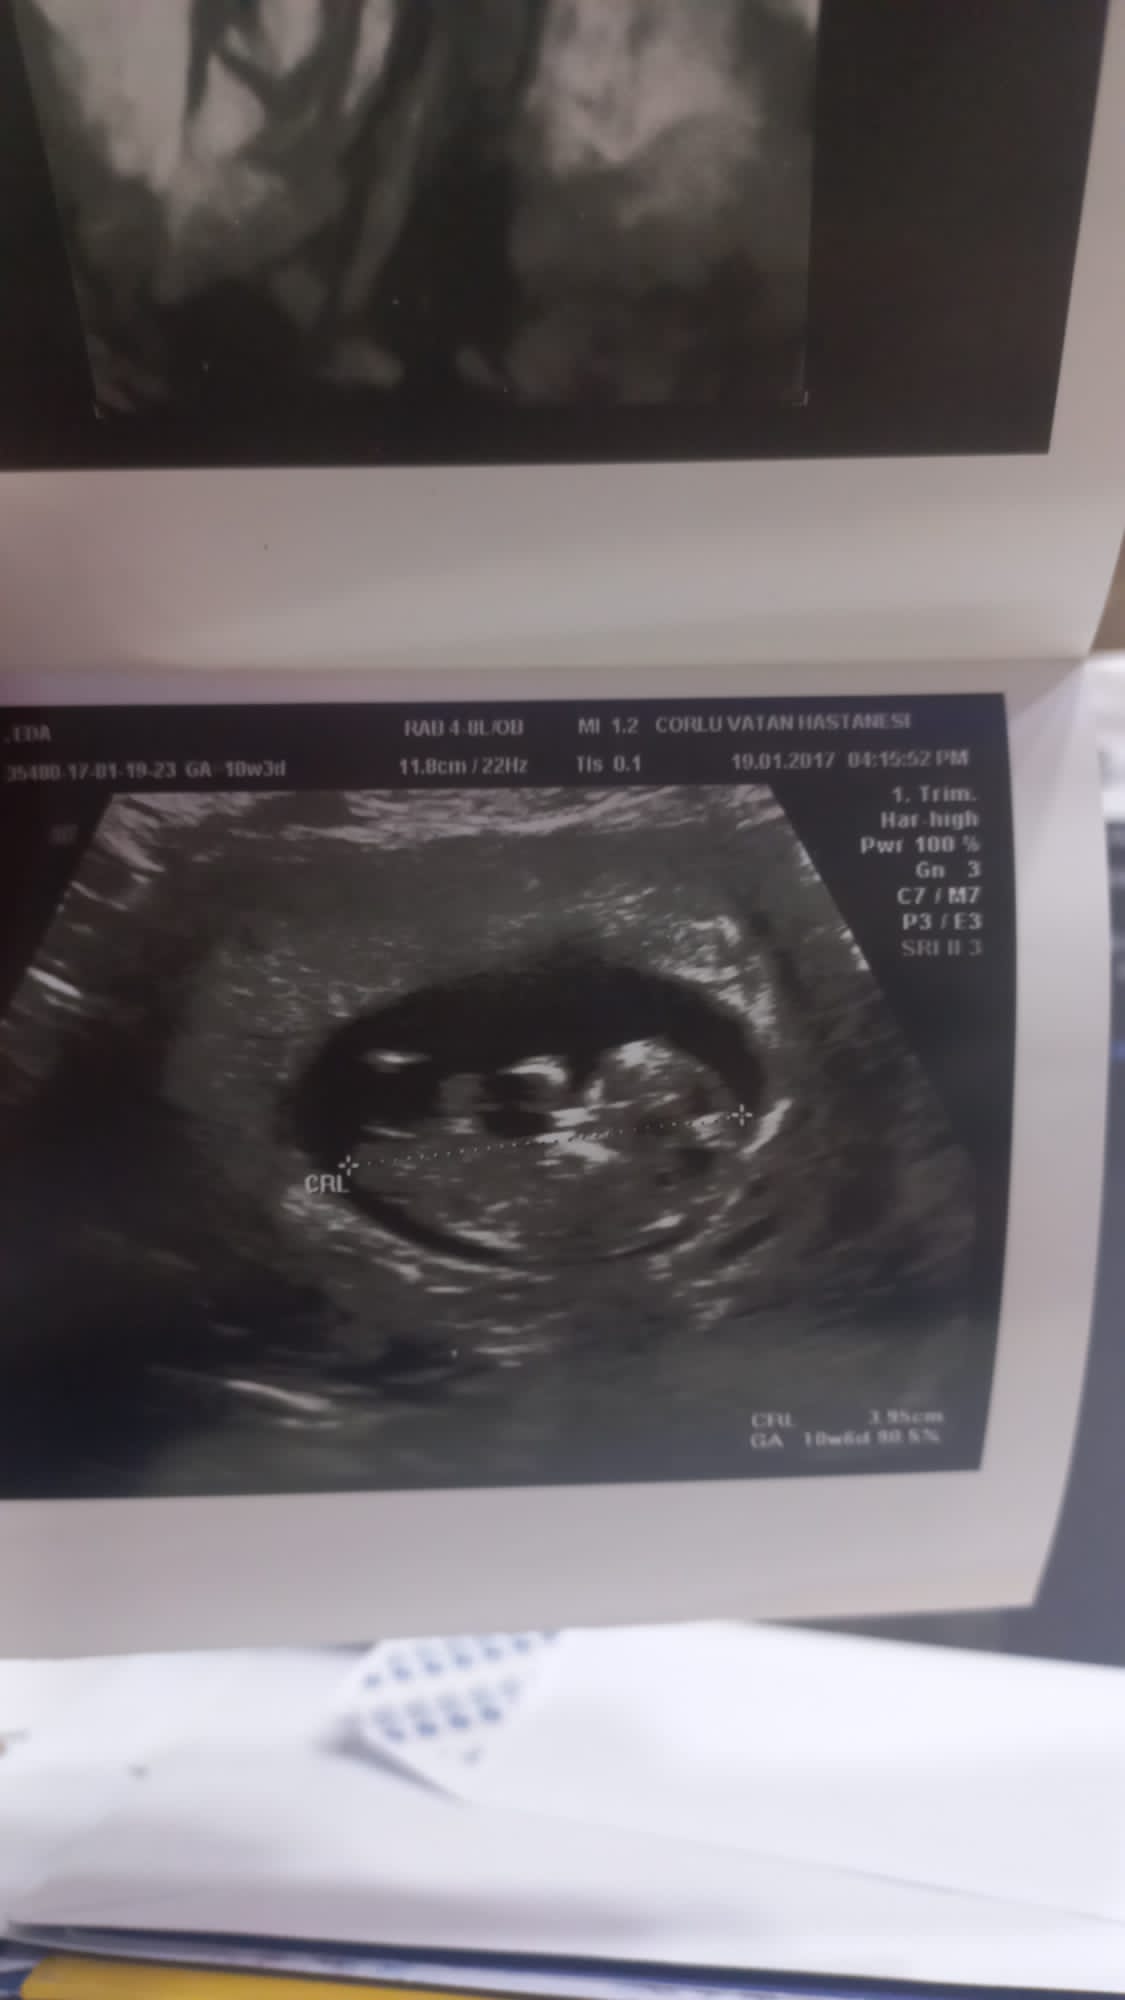

Merhabalar tekrardan 11 haftalk olmuşuz yorum yaparmısınız çok teşekkür ederim